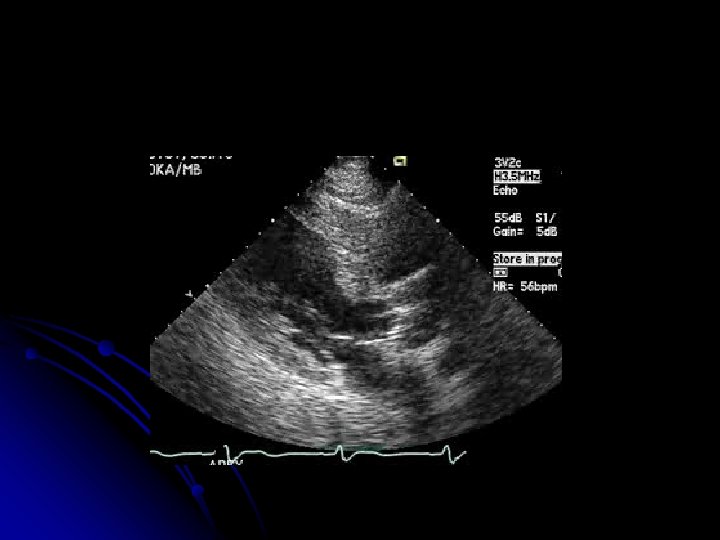

MVA =. 982 cm² MVA = 1. 84 cm² PRE-PROCEDURE POST-PROCEDURE